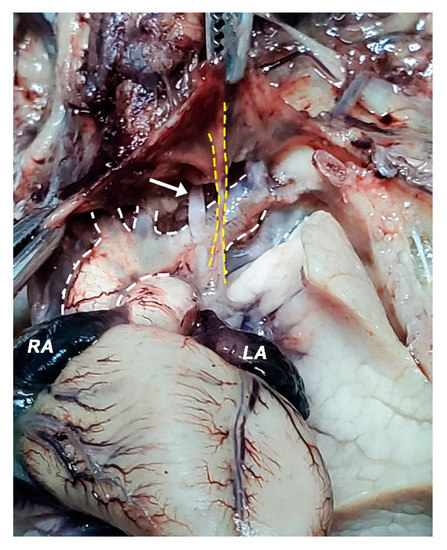

2.2. Dissection